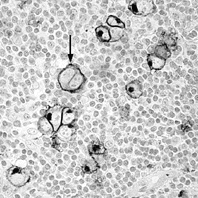

HLの組織像は様々な炎症性背景に数の少ない、大型の特異細胞が散見されるのが基本像である。新WHO分類では典型的なHRS細胞の出現するclassical HL(CHL)とpopcorn細胞の出現するnodular lymphocyte predominance HL(NLPHL)とに大別され、CHLはさらにlymphocyte rich (LR), mixed cellularity (MC),nodular sclerosis (NS),lymphocyte depletion(LD)の4型に細分される。H/RS細胞は小リンパ球より大きい光輝性核小体がみられ、その周りに明庭を有する大きな核をもつ細胞で、単核のものをH(Hodgkin)細胞、2核以上のものをRS(Reed-Sternberg)細胞という(図1,2,3)。多分葉の核をもつ細胞をpopcorn細胞と言う(図4)。

図1. Hodgkin lymphoma光顕像 H.E染色

炎症性細胞が混在する背景に大型の特異細胞(腫瘍細胞)が散見される。